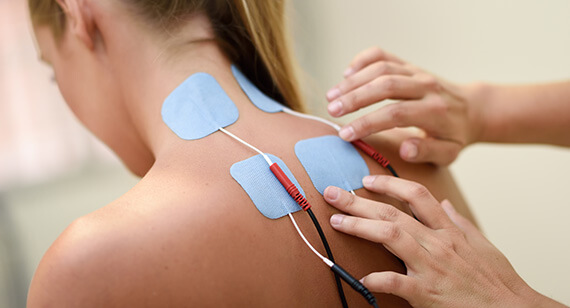

Physio Therapy

Physiotherapists spend years studying how the body works, how injuries impact performance & how to recover and repair injured tissues.

Physiotherapists spend years studying how the body works, how injuries impact performance & how to recover and repair injured tissues.

Read morePhysiotherapy

A personal injury from vehicle accident trauma is common many times effects of an vehicle injury are delayed or subtle.